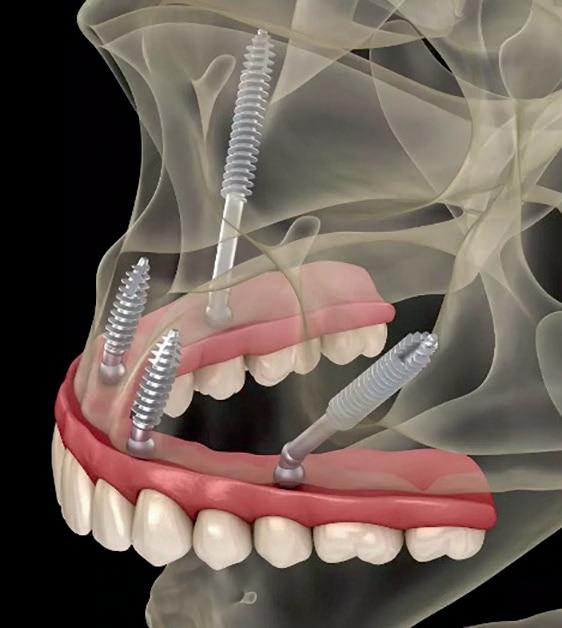

Fixe Zähne ohne Knochenabbau an nur einem Tag

Was die Menschen oft davon abhält, den Zahnarzt für Hilfe aufzusuchen, ist die Angst vor langen und schmerzhaften Behandlungen, welche mehrere Eingriffe und lange Wartezeiten mit sich bringen. Die All-onX-Methode kann dabei Abhilfe schaffen.

Was ist All-on-X?

Diese Methode ist eine Weiterentwicklung der „All­on­4“Technik in der Zahnimplantologie, bei der „X“ für die Anzahl der Implantate steht. Während bei der All­on­4­Methode vier Implantate verwendet werden, kann bei der All­on­X­Methode die Anzahl variieren. Häufig werden zwischen 4 und 8 Implantaten eingesetzt, um die bestmögliche Stabilität und Funktionalität des Zahnersatzes zu gewährleisten. Dabei werden die Implantate nicht nur im Kieferknochen stabilisiert, sondern bei fortgeschrittenen Fällen auch im Jochbein, Keilbein oder Nasenbein.

Prinzip und Vorteile von All-on-X

1. Anzahl der Implantate: Die genaue Anzahl der benötigten Implantate wird durch den Zustand des Kieferknochens und die individuelle Anatomie des Patienten bestimmt. Ziel ist es, eine lange Heilungsdauer zu vermeiden und auch bei hochgradigem Knochenschwund sofort feste Zähne befestigen zu können.

2. Individuelle Anpassung: Der Vorteil von All­on­X liegt in der Flexibilität – je nach Knochenqualität und Kieferstruktur wird entschieden, wie viele Implantate nötig sind, um eine stabile und langlebige Lösung zu gewährleisten.

3. Geringerer Eingriff: Wie bei der All­on­4­Methode erfolgt auch bei der All­onX­Behandlung der Eingriff minimalinvasiv und ohne die Notwendigkeit eines aufwendigen Knochenabbaus, da die Implantate strategisch gesetzt werden, um das vorhandene Knochenmaterial bestmöglich zu nutzen.

4. Feste Zähne: Bei All­on­X kann eine feste Brücke auf den Implantaten befestigt werden, wo die traditionelle All­on4­Methode an ihre Grenzen kommt. Der Vorteil ist, dass der Patient wieder über feste, funktionale Zähne verfügt, die optisch natürlichen Zähnen sehr nahekommen.

Was sind Jochbeinimplantate?

Zygoma oder Jochbeinimplantate sind eine spezielle Art von Zahnimplantaten, die für Patienten entwickelt wurden, bei denen der Kieferknochen stark geschwunden oder nicht ausreichend vorhanden ist, um herkömmliche Implantate zu stützen. Diese Implantate werden nicht im Kieferknochen, sondern in den Jochbeinbereich (Zygoma) eingesetzt, also in den Knochen, welche den Wangenknochen bilden. Der Vorteil dieser Implantate ist die hohe Stabilität im Jochbein. Sie können somit sofort mit festen Zähnen belastet werden.

Was sind pterygoide Implantate?

Pterygoide Implantate sind Zahnimplantate, die in den Processus pterygoideus des Keilbeins gesetzt werden. Sie sind besonders nützlich bei Patienten mit starkem Knochenschwund im hinteren Oberkiefer, wo herkömmliche Implantate nicht genügend Halt finden. Sie kommen gänzlich ohne langwierige Knochenabbauten aus und können sofort mit festen Zähnen verbunden werden.

Was sind transnasale Implantate?

Transnasale Implantate sind eine spezialisierte Form von Zahnimplantaten, die im Oberkiefer durch die Nasenhöhle hindurch in den Knochen des Nasenbodens oder der Nasenrückenregion verankert werden. Sie werden meist verwendet, wenn aufgrund von starkem Knochenschwund keine ausreichende Knochensubstanz im Oberkiefer vorhanden ist. Diese Implantate sind sehr stabil und können ebenfalls sofort mit Zähnen belastet werden.

Diese Methode ermöglicht auch bei fortgeschrittenem Knochenabbau feste Zähne bei einem Eingriff.